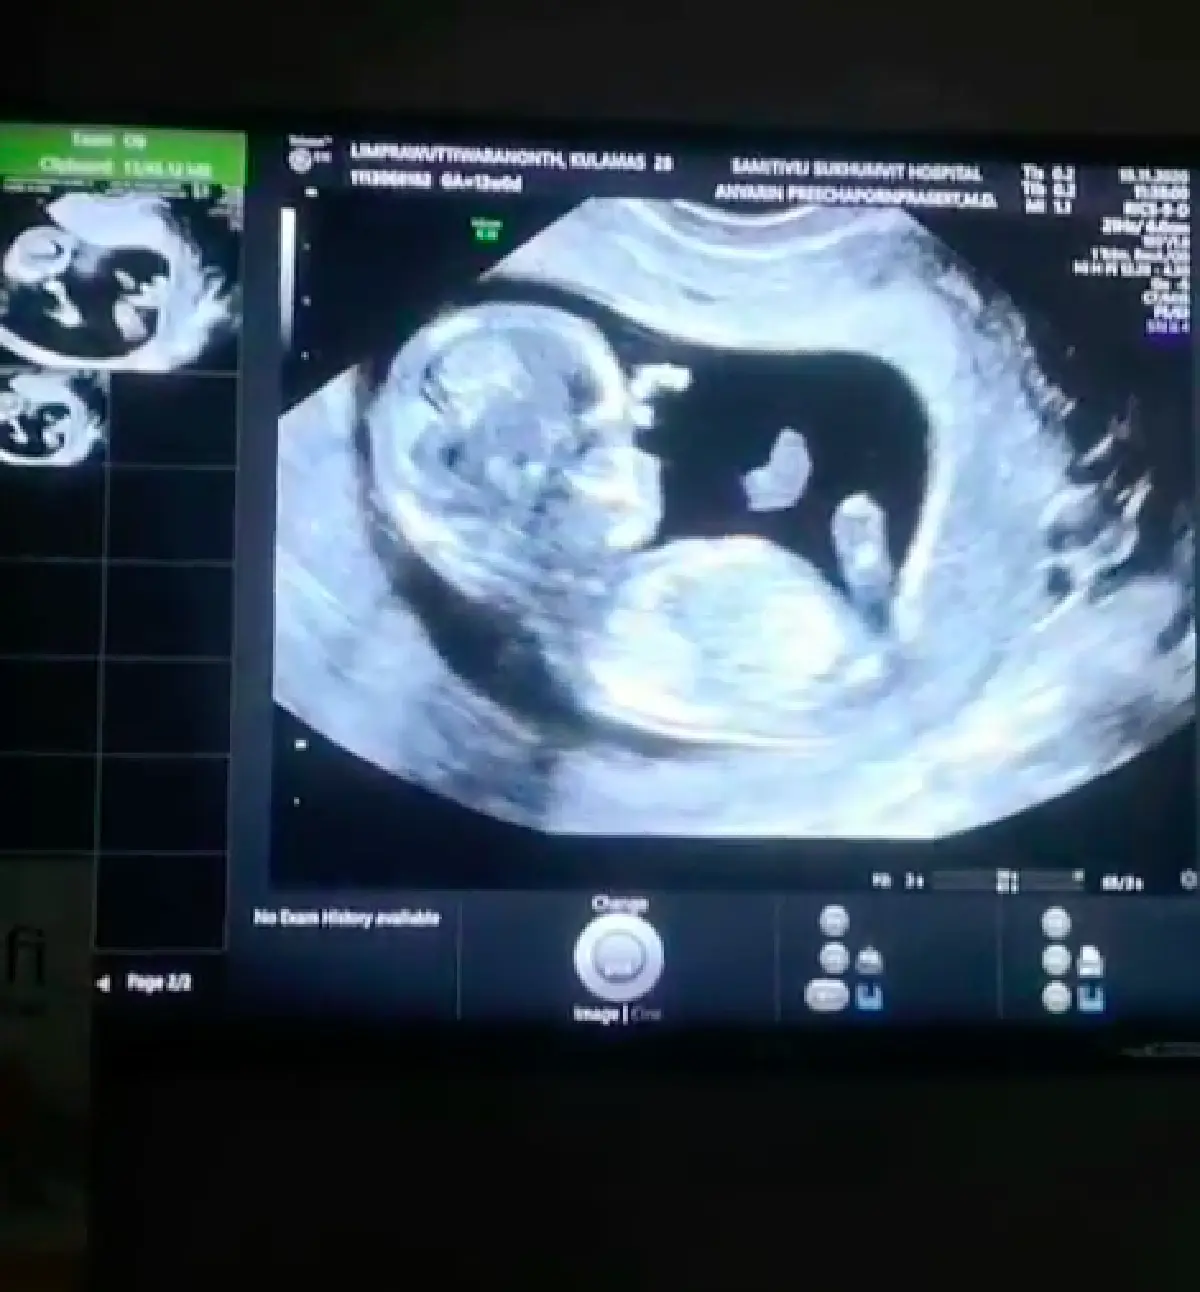

เบบี๋มาแล้ว! “ขนมจีน กุลมาศ” ตั้งท้องลูกคนแรก 13 สัปดาห์ พร้อมเผยภาพอัลตราซาวด์ให้ได้ชมกัน

ซึ่งทางสาว “ขนมจีน” ได้ออกมาประกาศข่าวดีผ่านทางอินสตาแกรม ว่าเธอนั้นกำลังตั้งครรภ์ลูกคนแรกได้ 13 สัปดาห์แล้ว พร้อมทั้งยังได้เผยภาพอัลตราซาวด์ให้ได้ชมกัน อีกทั้งเธอนั้นยังได้บอกว่า